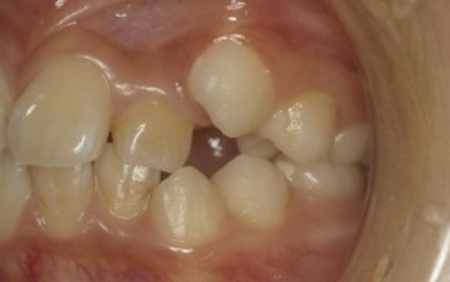

10代女性 乱れた歯並びと噛み合わせをワイヤー矯正で改善した症例

「歯並びが悪い。とくに八重歯が気になる」とご相談いただきました。

拝見したところ、上下の前歯を中心に、歯が正常な位置からずれたりねじれたりしてデコボコに生えている状態でした。

以上のことから、歯並びを改善する必要があると診断しました。